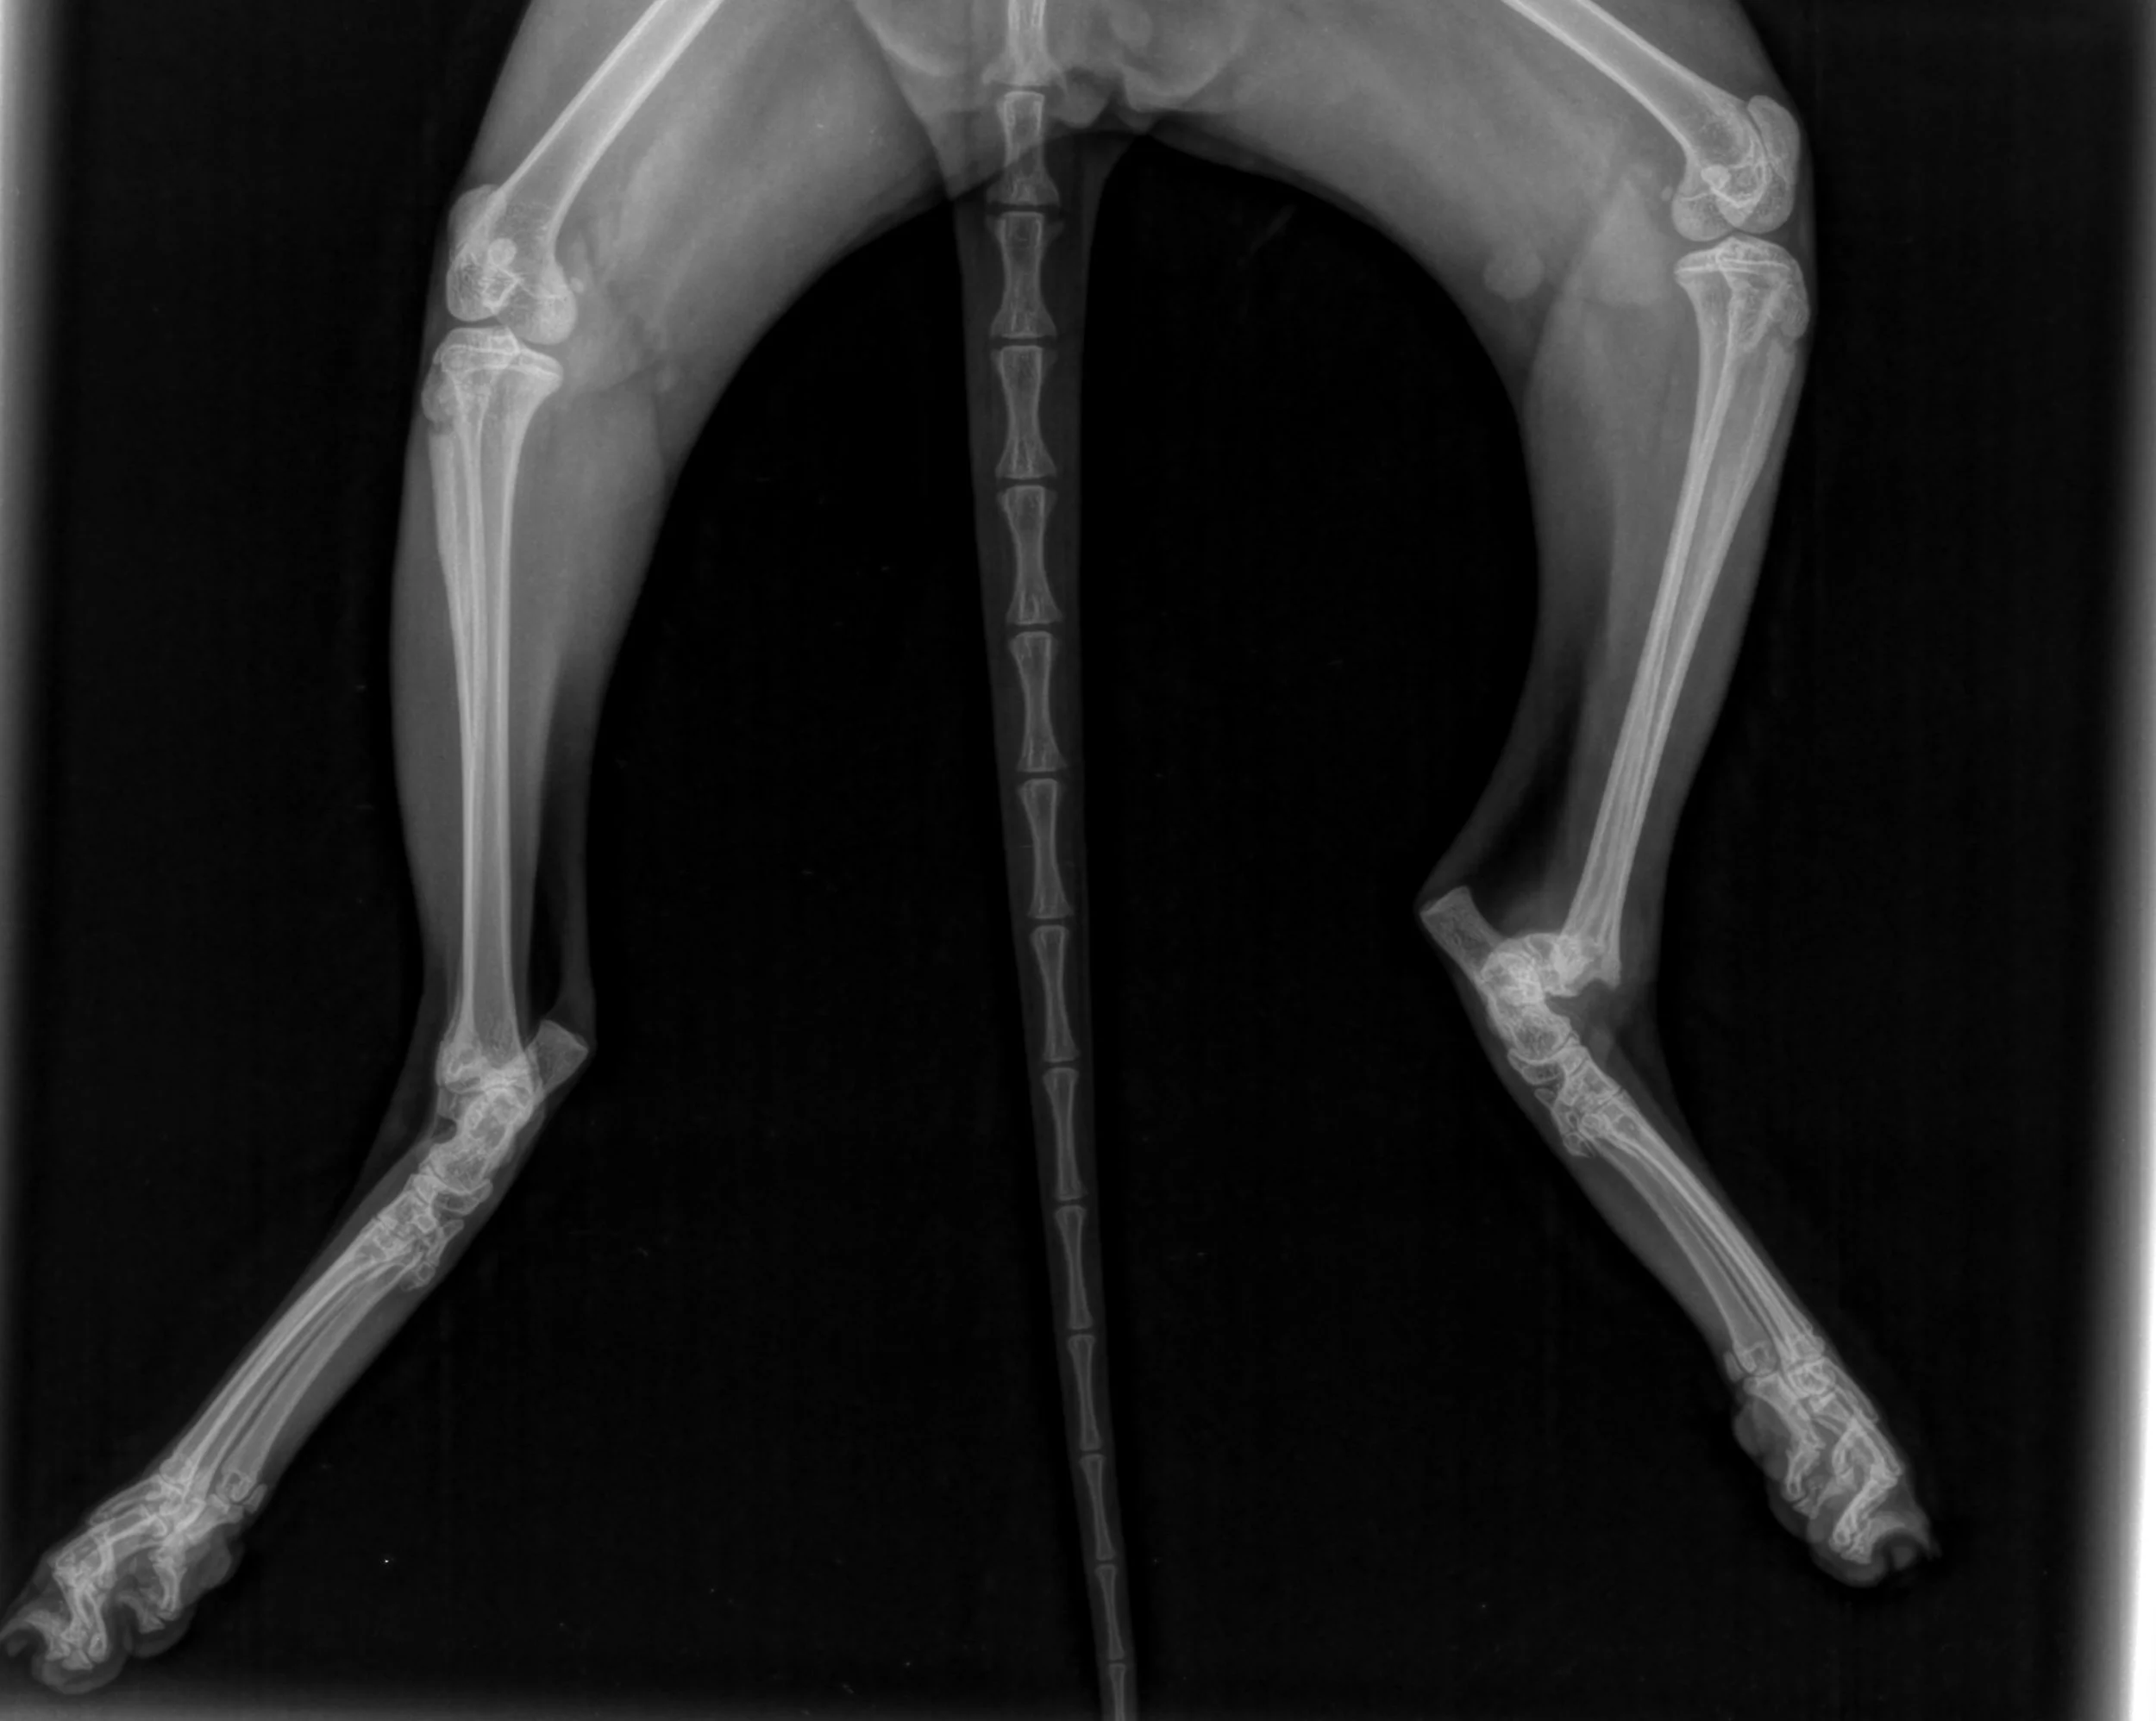

A male doctor in teal scrubs with a stethoscope around his neck giving a presentation in front of a group, with a poster showing a fracture repair X-ray of a leg with a metal plate.